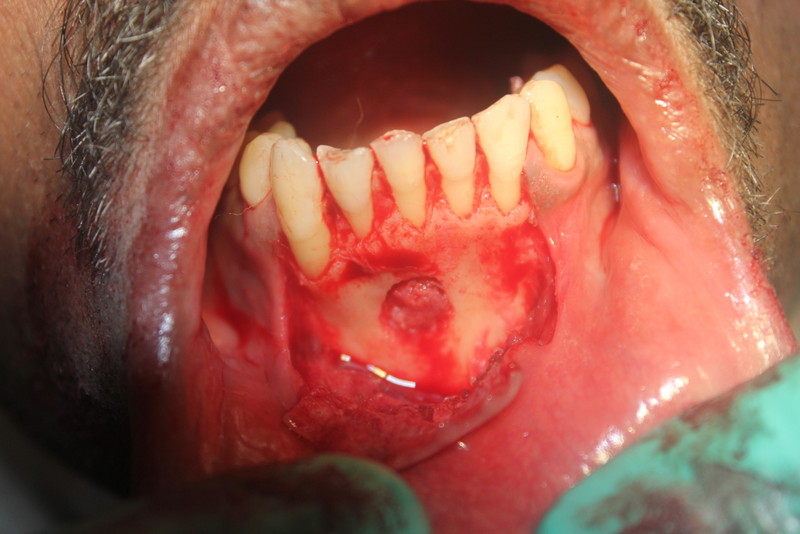

Apicoectomy